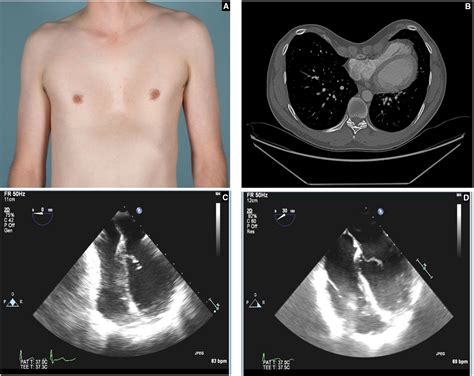

Pectus excavatum, a condition characterized by a concave or sunken chest, can significantly impact an individual's quality of life. This condition, often present from birth, can cause various physical and psychological issues. One of the most effective treatments for pectus excavatum is the Nuss Surgery Pectus Excavatum procedure. This minimally invasive surgery has revolutionized the treatment of this condition, offering patients a chance to improve their chest appearance and respiratory function.

Pectus excavatum is a congenital deformity where the sternum and rib cage grow abnormally, causing the chest to cave in. This condition can vary in severity, with some individuals experiencing mild symptoms while others face significant health issues. Common symptoms include:

• Enhanced Respiratory Function: By correcting the chest shape, the procedure can improve lung capacity and respiratory function, reducing symptoms such as shortness of breath and fatigue.

• Pneumothorax: A collapsed lung can occur during or after the surgery.